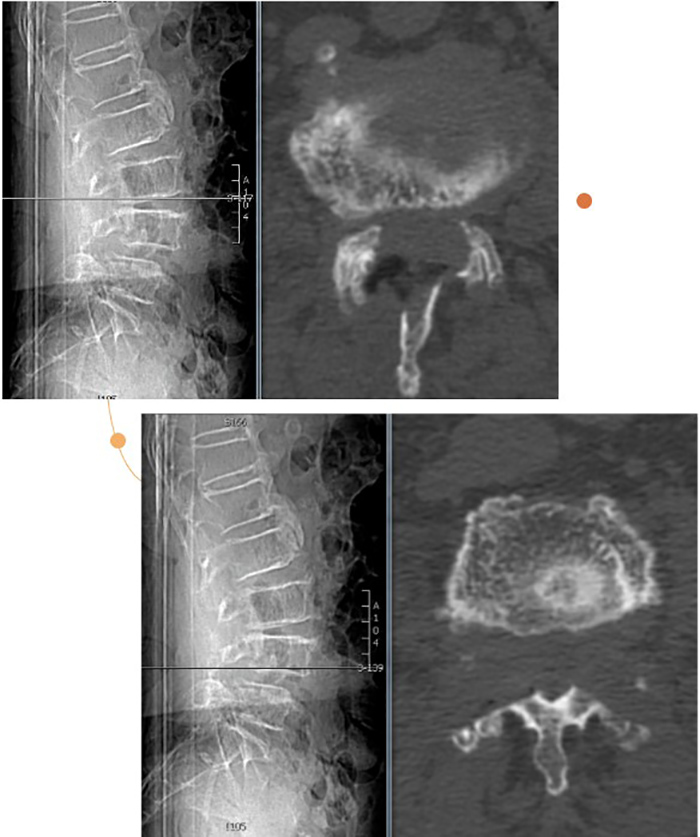

术前影像

经过详细的术前评估和完善的术前准备,陈瑞松带领团队为张阿婆进行一个节段的单侧入路双侧减压(ULBD)手术及一个节段的双侧入路270度减压手术,仅切开了三个7毫米的小切口,一个多小时就顺利完成手术。